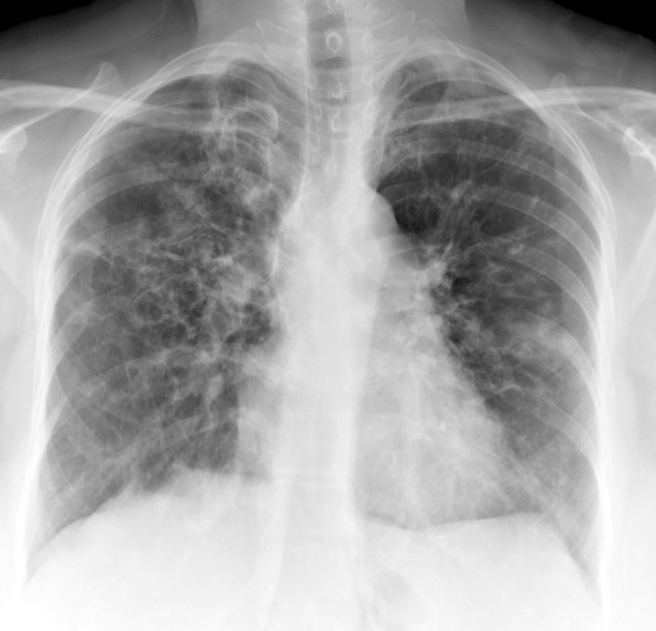

Gallery COPD ABPA PA

ABPA PA